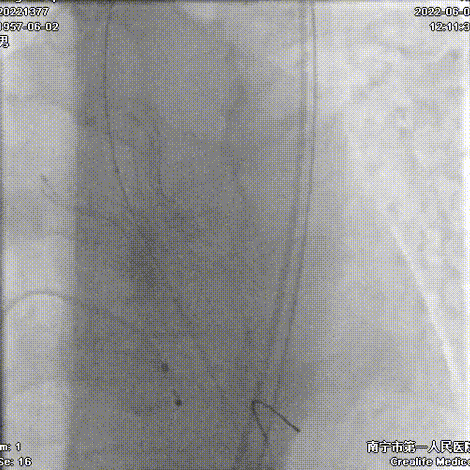

手术过程:

导丝跨瓣

20mm球囊预扩

Snare协助输送器跨瓣

AV26瓣膜定位

AV26瓣膜释放到工作位

AV26瓣膜释放

22mm球囊后扩

术后主动脉根部造影,形态改善

本例手术为重度钙化二叶式病变重度主动脉瓣狭窄TAVR手术,团块状钙化挤压存在移位瓣周漏风险,术前手术团队对患者进行了全面细致的评估,确定假体瓣膜锚定区域范围,制定术前释放策略。球囊第一次通过困难,刘主任当机立断,采用外周小球囊预扩策略,再上20mm主动脉球囊充分预扩。通过球扩预判,果断采取snare辅助输送器顺利跨瓣。

刘杰主任团队通力配合、精准释放,充分利用TaurusElite可回收功能,在瓣膜释放至2/3时,多角度评估瓣膜植入深度、锚定力以及冠脉灌注情况,确认瓣膜植入深度合适、锚定力稳定,缓慢逐个脱钩,进行瓣膜释放。释放后造影显示钙化挤压严重,瓣膜膨胀不良,故选择球囊后扩,后扩后造影显示瓣膜膨胀良好,行血流动力学评估,跨瓣压差从术前220mmHg降至5mmHg,无明显瓣周漏,手术圆满完成。术后10小时拔管,第二天正常下床活动,术后5天出院。